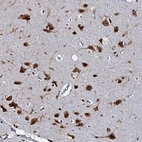

Immunohistochemical staining of human colon shows strong nuclear positivity in glandular cells.